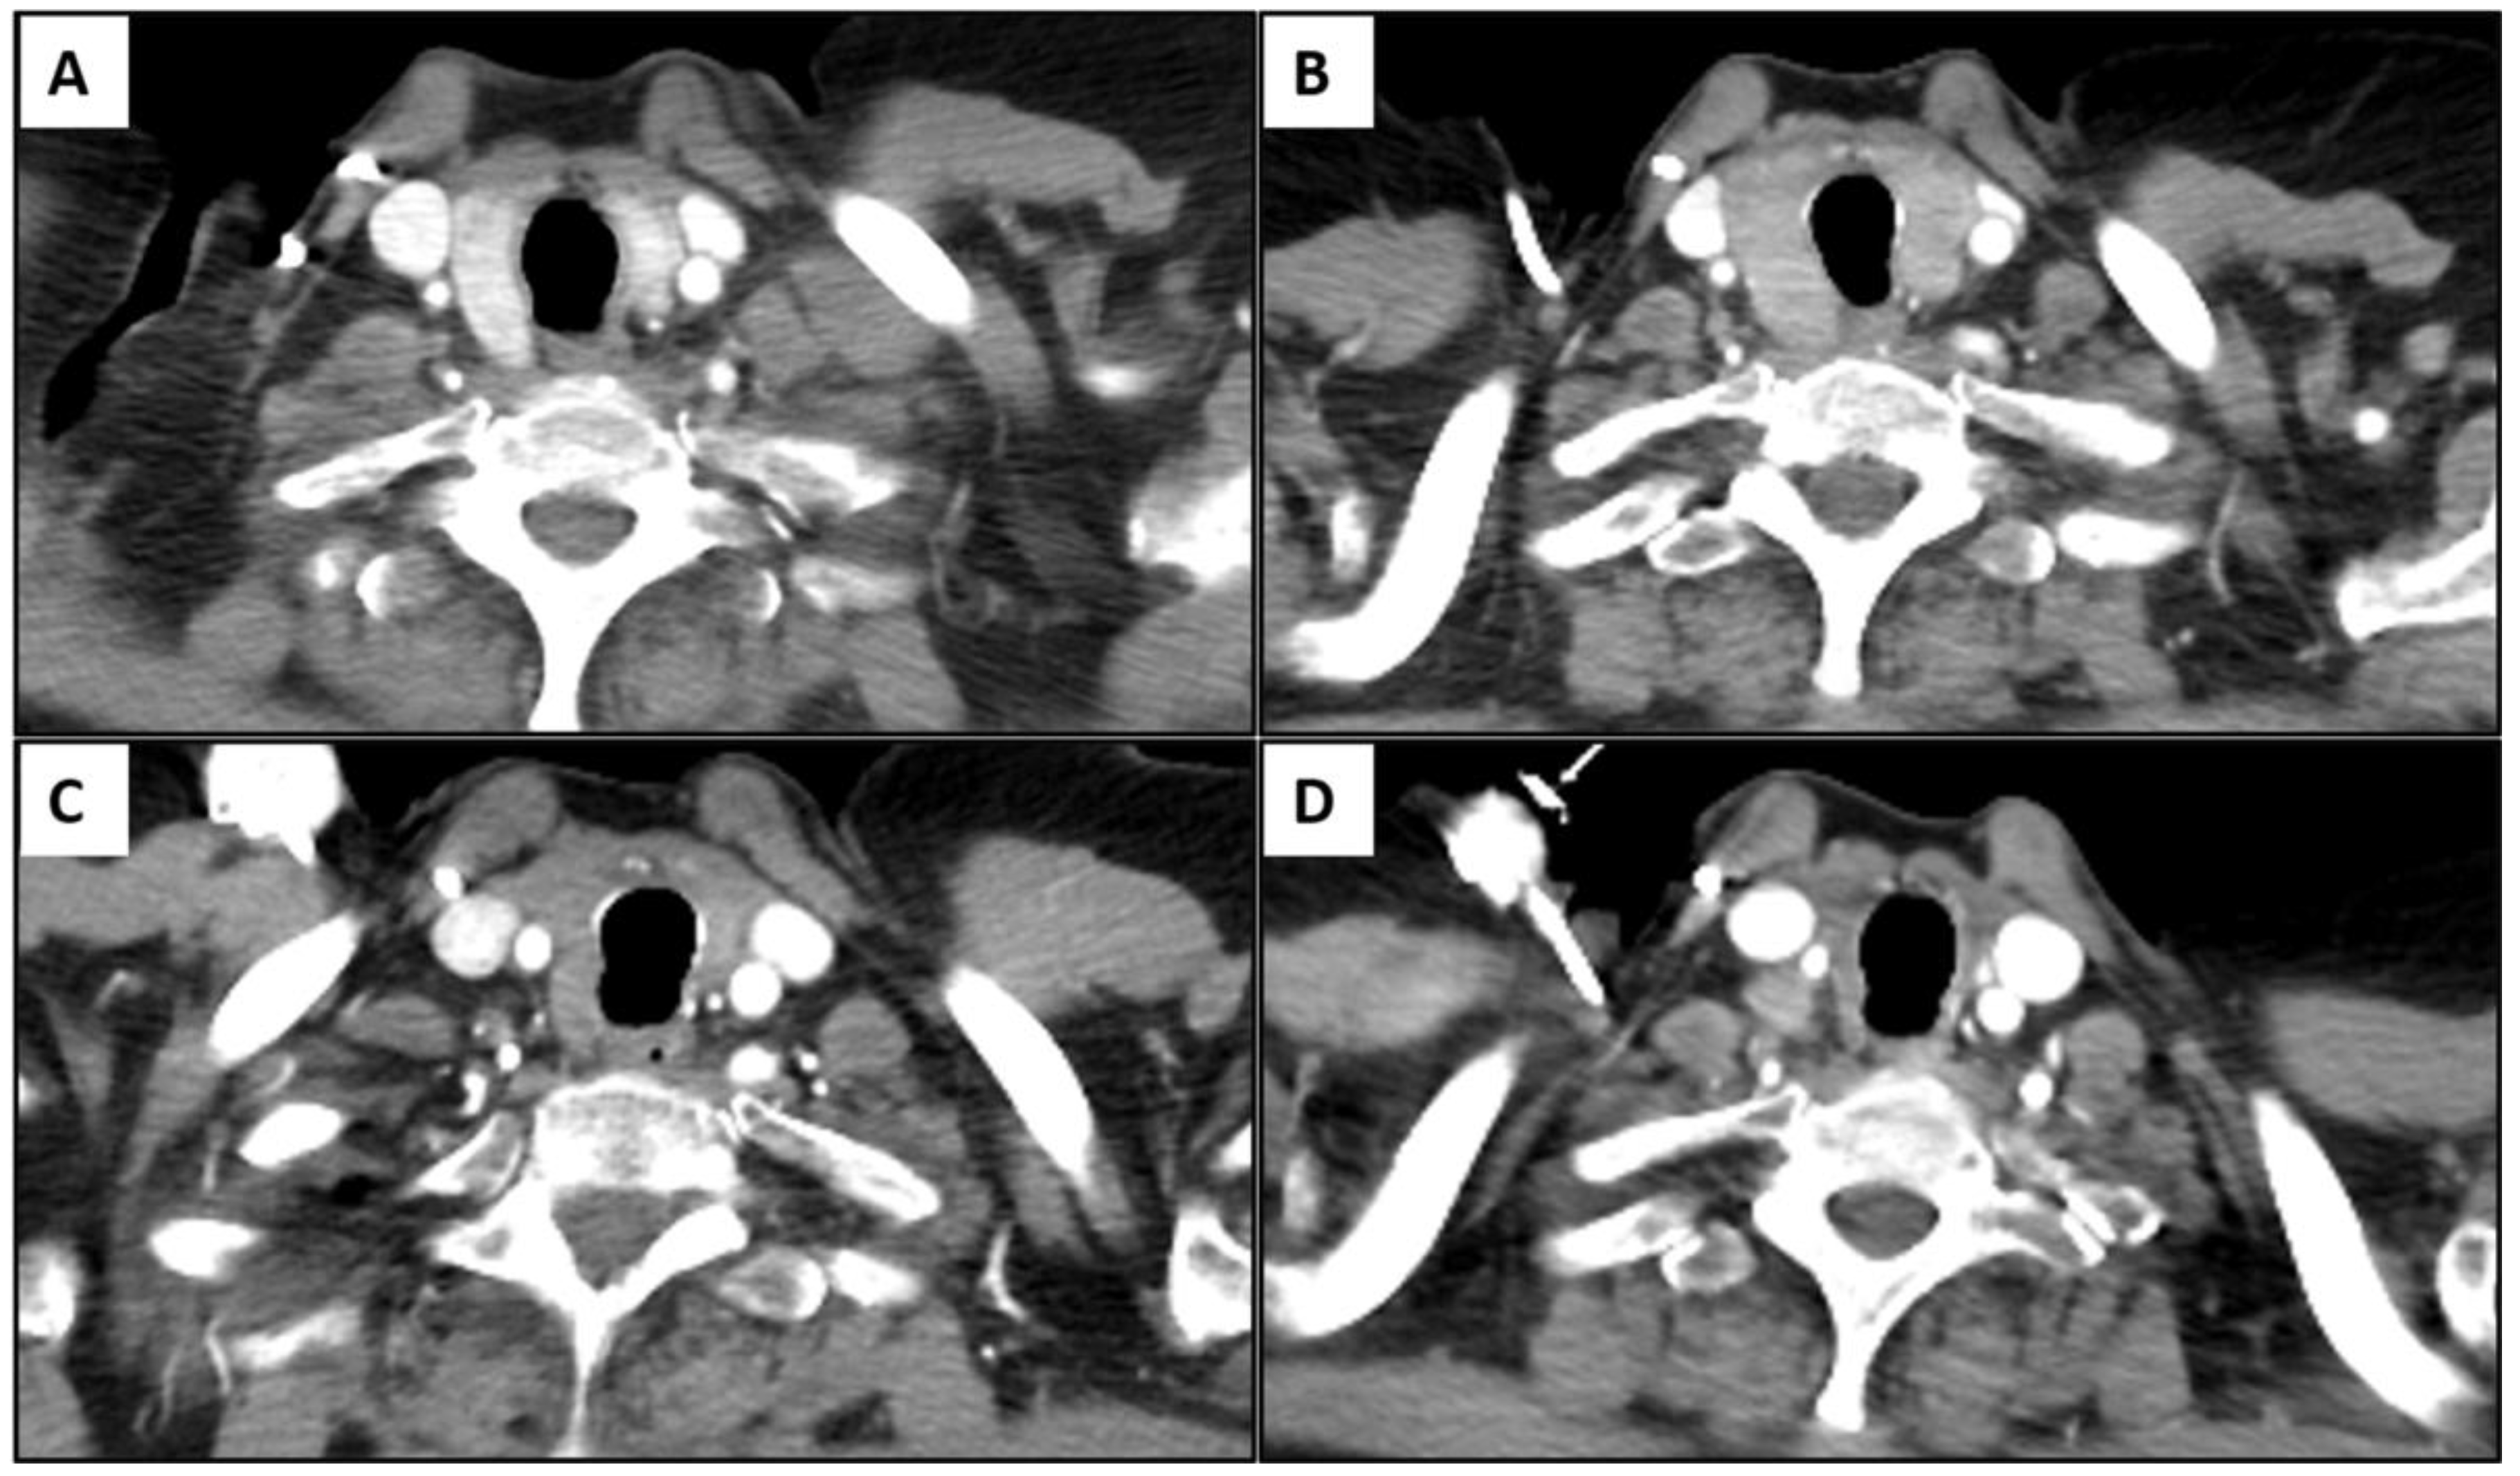

Among 22 patients, 11 patients showed an unchanged size or enlargement of the gland with heterogeneous or diffuse hypoattenuation of the gland on the initial positive scan, and 10 patients eventually showed atrophy of the gland with heterogeneous or diffuse hypoattenuation of the gland on follow-up CT scans (mean: 5.8 weeks; range: 1.4 to 14.4 weeks); additionally, one patient had no follow-up imaging. Eleven patients with atrophy of the gland with heterogeneous or diffuse hypoattenuation of the gland on the initial positive CT scan demonstrated progressive atrophic changes in follow-up studies (Figure 5).

Figure 5.

Representative case of temporal change in immune-related thyroiditis. A 70-year-old female with advanced lung cancer treated with ipilimumab and pembrolizumab combination therapy. There was interval enlargement of thyroid gland with diffuse hypoattenuation (B) compared to the baseline study (A) after 3.9 weeks of therapy. On follow-up scan after 12 weeks of therapy (C), the gland became atrophic and progressed in serial follow ups. End-of-therapy scan (after 2 years of therapy) showed significant atrophy of gland (D). The patient experienced transient thyrotoxicosis followed by hypothyroidism which required hormone replacement.